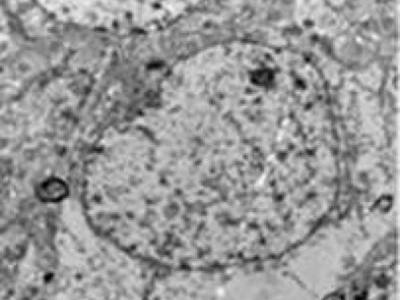

注射dl-3n丁基苯酞后,弥漫性脑损伤大鼠的大脑皮质神经细胞损伤明显减轻,核仁清...